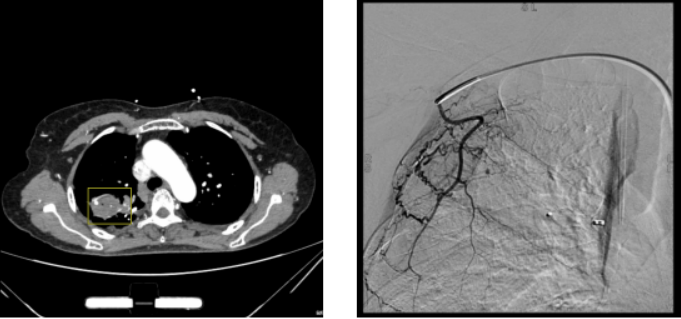

上述两个病例分别为PAPs造影分型的A型和B型,此类患者首先需要通过胸部CT发现PAPs,如果没有发现,按照常规流程后续需行支气管动脉栓塞,很容易被遗漏,且止血困难。患者⼥性,50岁,右上肺空洞型肺结核,侵袭性肺曲霉病。大咯血,于外院行支气管动脉栓塞,仍无法止血。考虑转运途中存在一定风险,我院团队至当地医院进行救治。支气管镜下清理血块,寻找出血位置,以便进行球囊保护,然后进行支架封堵,为外科手术或血管栓塞创造机会。封堵支架为房间隔封堵器(下图所示),但其并无肺内使用指征,通过医院伦理审查予以使用。支架置入后患者情况较稳定,转至我院继续治疗。入院后经检查发现PAPs,该动脉瘤是由锁骨下动脉分出的胸廓动脉供血,遂行右侧胸外侧动脉栓塞微球栓塞。这一病例提示我们,进行动脉栓塞时,除了支气管动脉,锁骨下动脉、胸廓动脉、腹腔干也应纳入,避免遗漏责任血管。